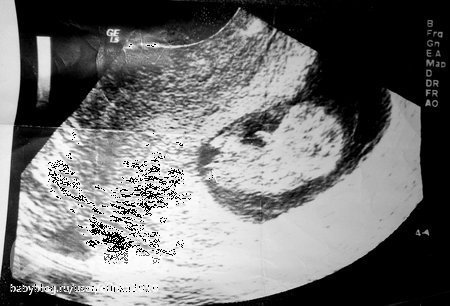

ФолликулометрияДевочки, была сегодня на УЗИ, Г сделала заключение - Эхографические признаки кистозно измененных яичников. И поставила диагноз: Дисфункция яичников ановуляционные циклы. Бесплодие первичное.

У меня ставили это диагноз с 14 лет и тоже самое говорили ,что бесплодие +дефицит массы тела ,поликистоз яичников.В позапрошлом году у меня была задержка на 3 месяца-пошли на узи ,посмотреть какая на этот раз киста у меня там -Результаты УЗИ были потрясающими